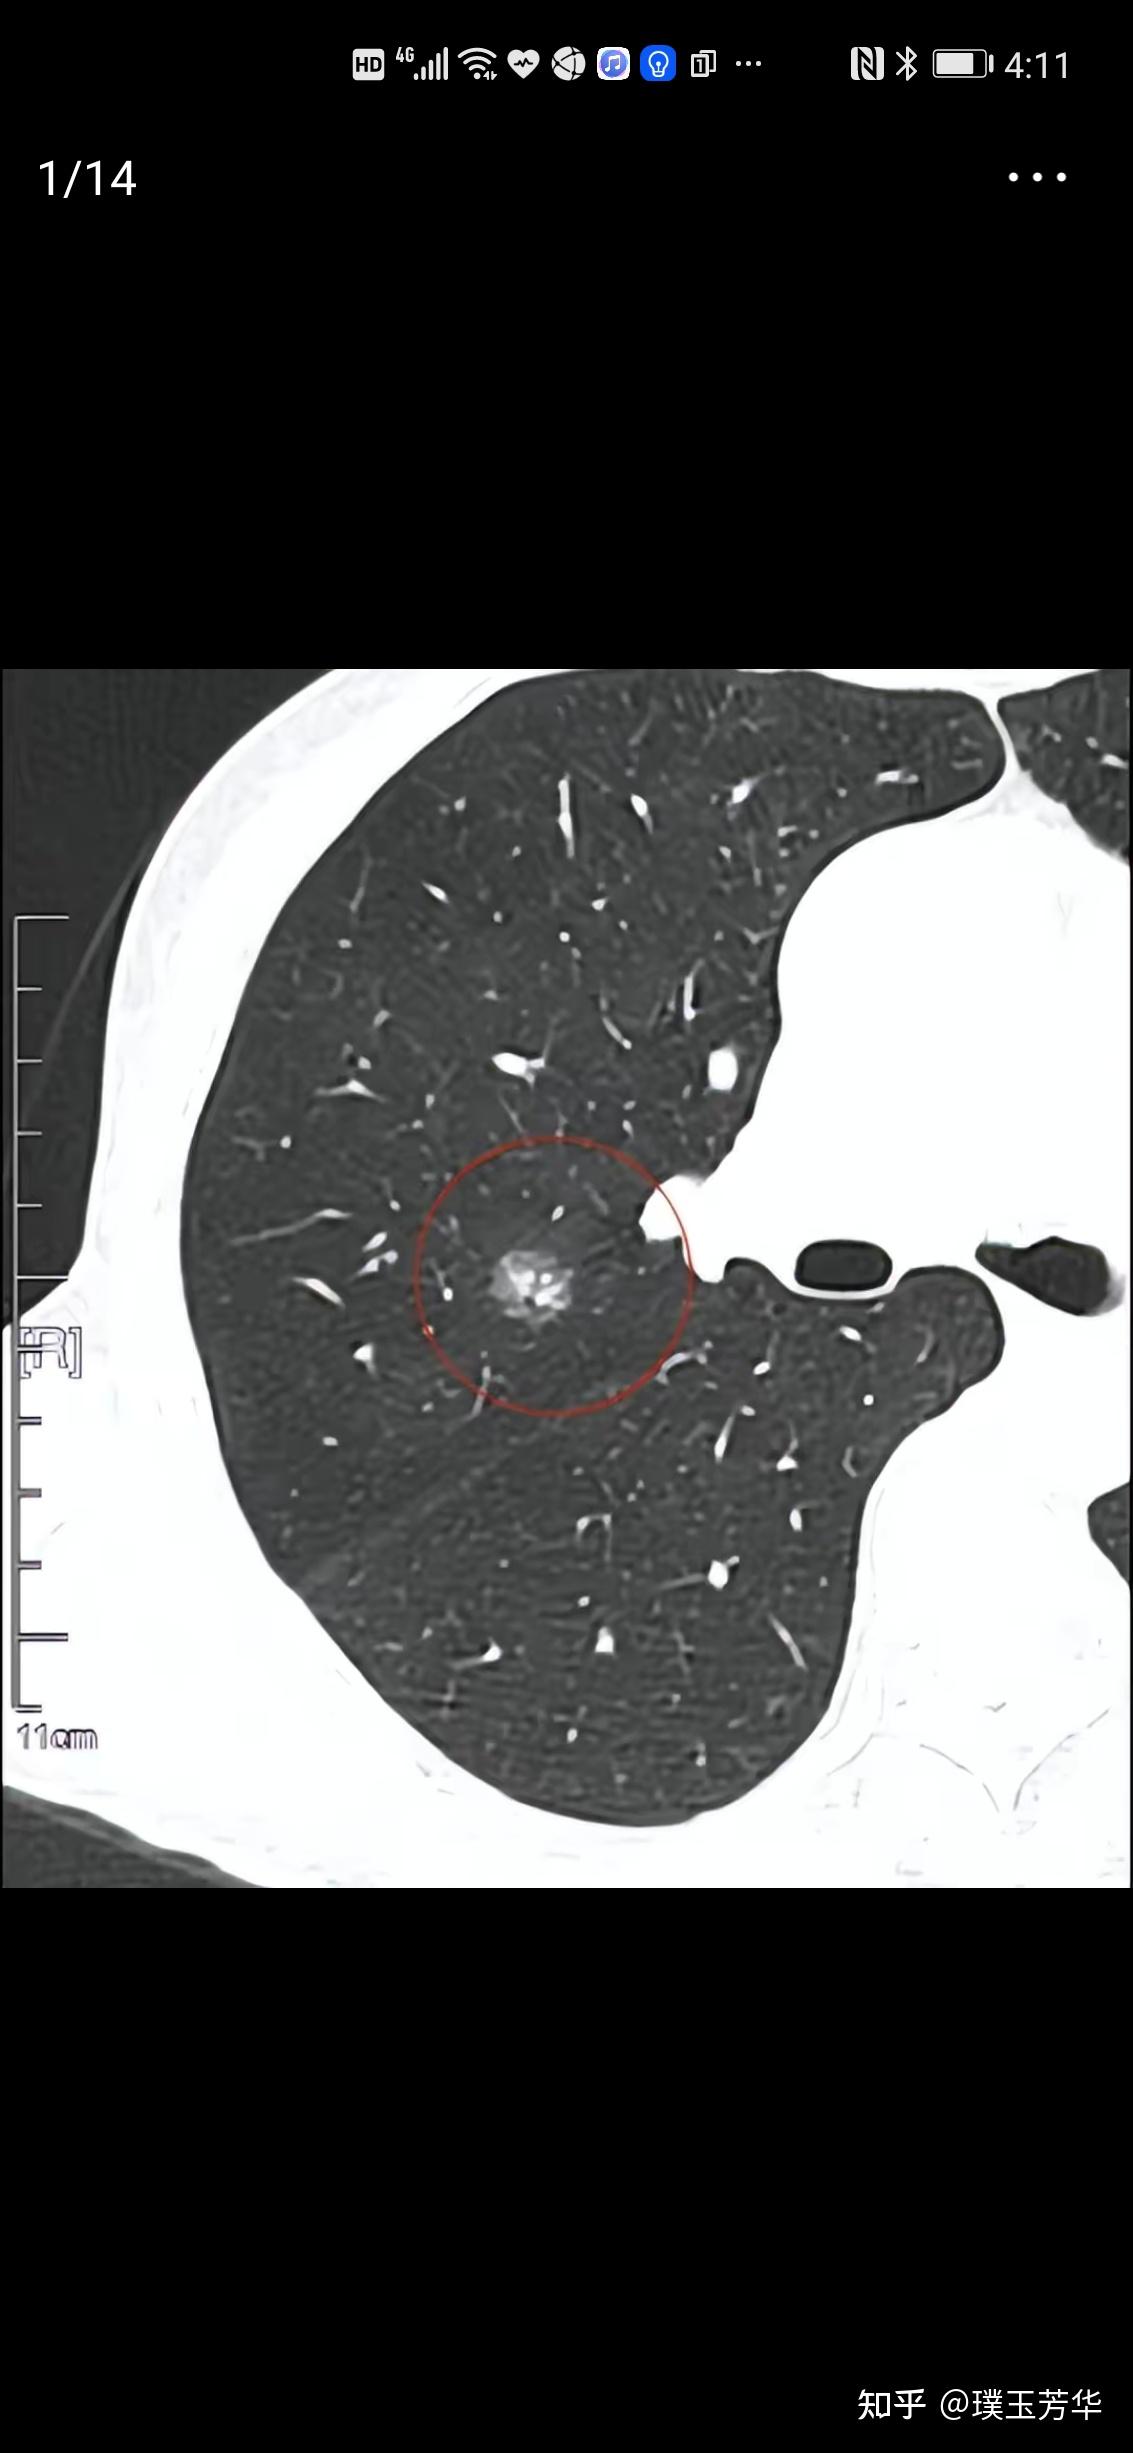

左下肺磨玻璃结节,求大神看片 [病例帖]